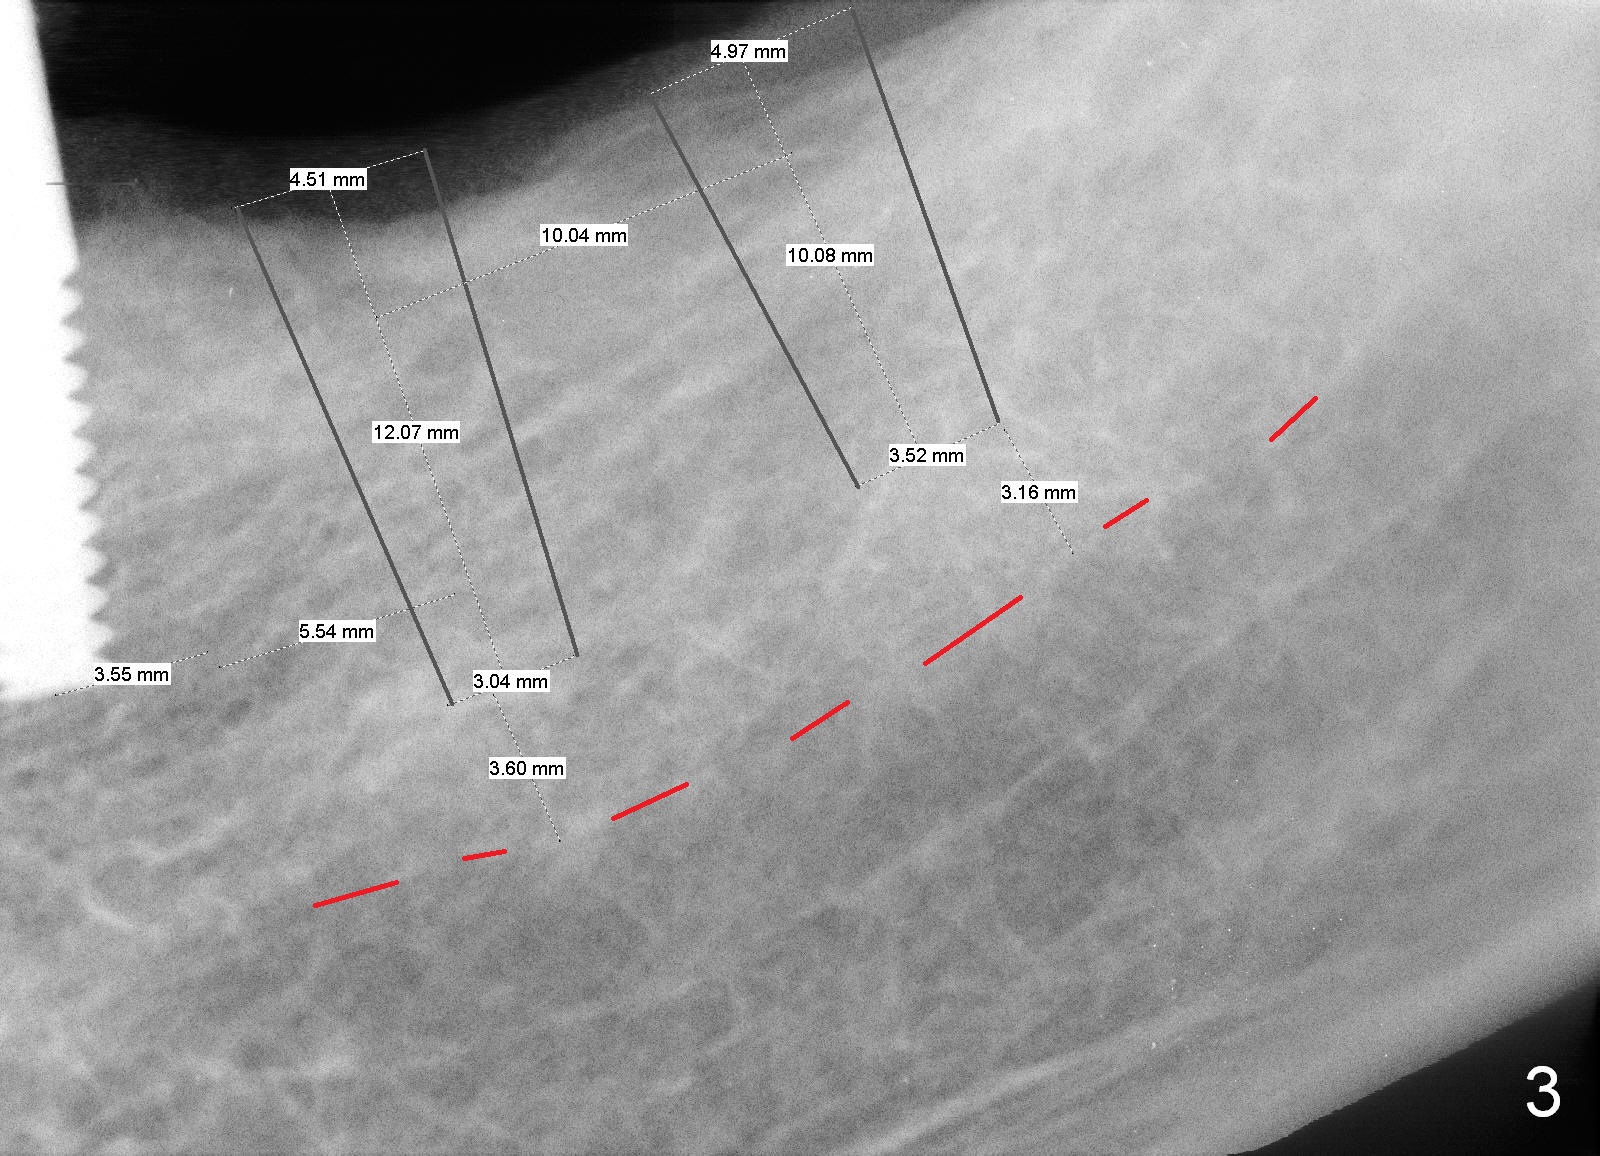

Last visit, a 76-year-old lady found that the tooth #24 was mobile. After #25 implant crown recementation, occlusal equilibrium was done so that occlsual force/contact was transferred from #24 to #25. Two weeks later, the tooth #24 mobility is reduced. The patient wants to crown the rest of the lower anterior teeth. After discussion, she agrees to restore the posterior teeth first. PAs and impression are taken (Fig.1-4). When the implant was placed at the site of #20 (Fig.1), the bone was found to be soft. To obtain primary stability, osteotomy at #18 and 19 will be under prepared (one size smaller). The immediate provisional at the site of #20 is oversized mesiodistally. Before surgery, it should be trimmed as shown in Fig.4 red dashed line. The 3 implants are to be splinted. No localized use of antibiotic is for this case, since these 2 teeth have been missing > 6 months.